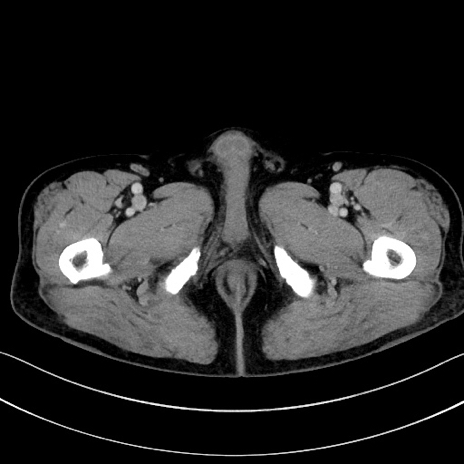

症例15(横断像)

【症例】70歳代男性

【主訴】腹痛

【現病歴】今朝から腹痛あり。全体的に痛い。特に左上の方。排ガスが今日はない。冷や汗が出る。

【既往歴】直腸癌術後

【身体所見】左側腹部〜上腹部に圧痛あり。腹膜刺激症状明らかなではない。軽度反跳痛。左下腹部に術後瘢痕あり。

【データ】WBC 7700、CRP 0.02